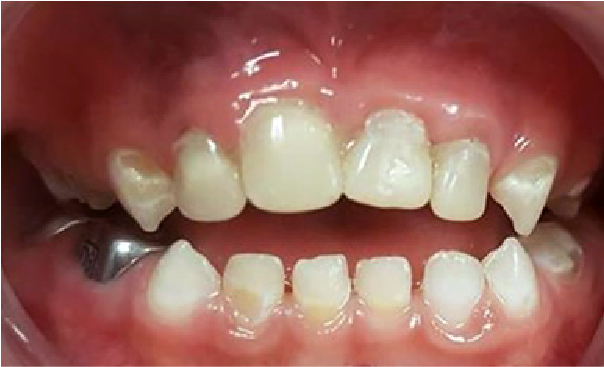

En la segunda cita, una semana después de la aplicación del barniz de flúor, se continuó con el mismo protocolo para colocar ahora el barniz de CHX (Cervitec® F), en esta semana se le indicó a los padres de la paciente que cambiaran de cepillo nuevamente y que todos los días efectuaran la higiene bucal con pasta dental sin flúor, ya que este podría inhibir el efecto de la CHX; otra de las indicaciones que se les dio fue colocar enjuague de CHX sobre las superficies dentarias con un cotonete después del cepillado dental en casa. Así por cuatro semanas alternando el barniz de CHX y flúor se logró la remineralización adecuada para continuar con el tratamiento restaurativo, las superficies dentarias se apreciaron con brillo natural, a la palpación con sonda periodontal punta roma ya no se sintieron superficies rugosas y frágiles (figura 5). Se procedió en las citas siguientes a llevar a cabo los tratamientos pulpares (pulpotomías) con sus coronas de acero cromo de los molares temporales; y el molar 75 se restauró con material bioactivo (Equia Forte) alternando el orden de los cuadrantes en cada cita para así mantener la conducta de la paciente, la cual en la escala de Frankl se definió como positiva (figura 6). Al restaurar el segmento anterosuperior se realizaron las pulpectomías de los dientes 51, 52, 61 y 62 para reconstruir el muñón (Equia Forte) y posteriormente se confeccionaron las coronas de celuloide de los órganos dentarios 51 y 52 (Cention) y los 61 y 62 con resina convencional (figura 7).

Figura 6. Vista oclusal de la arcada inferior con todos los órganos dentales restaurados.

Figura 7. Vista oclusal de la arcada inferior con todos los órganos dentales restaurados.